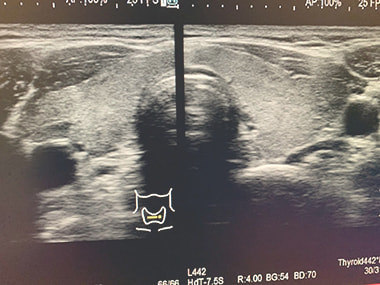

甲状腺エコー検査:

甲状腺の大きさ・腫瘍(のう胞・腺腫・がん)の有無などを調べます。

炎症・良性悪性腫瘍の診断に役立ちます。

甲状腺